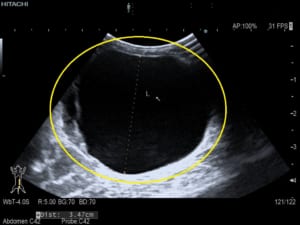

エキゾチック獣医は、身体検査を行っているときに、腹部の不快感とともにモルモットの内部に大きな嚢胞または一対の嚢胞を感じることがあります。獣医師は、嚢胞性卵巣の有無を確認するために X 線または腹部超音波検査を推奨する場合があります。診断を行うために、腹部と嚢胞に針を挿入して嚢胞内の液体を採取しようとすることもあります。